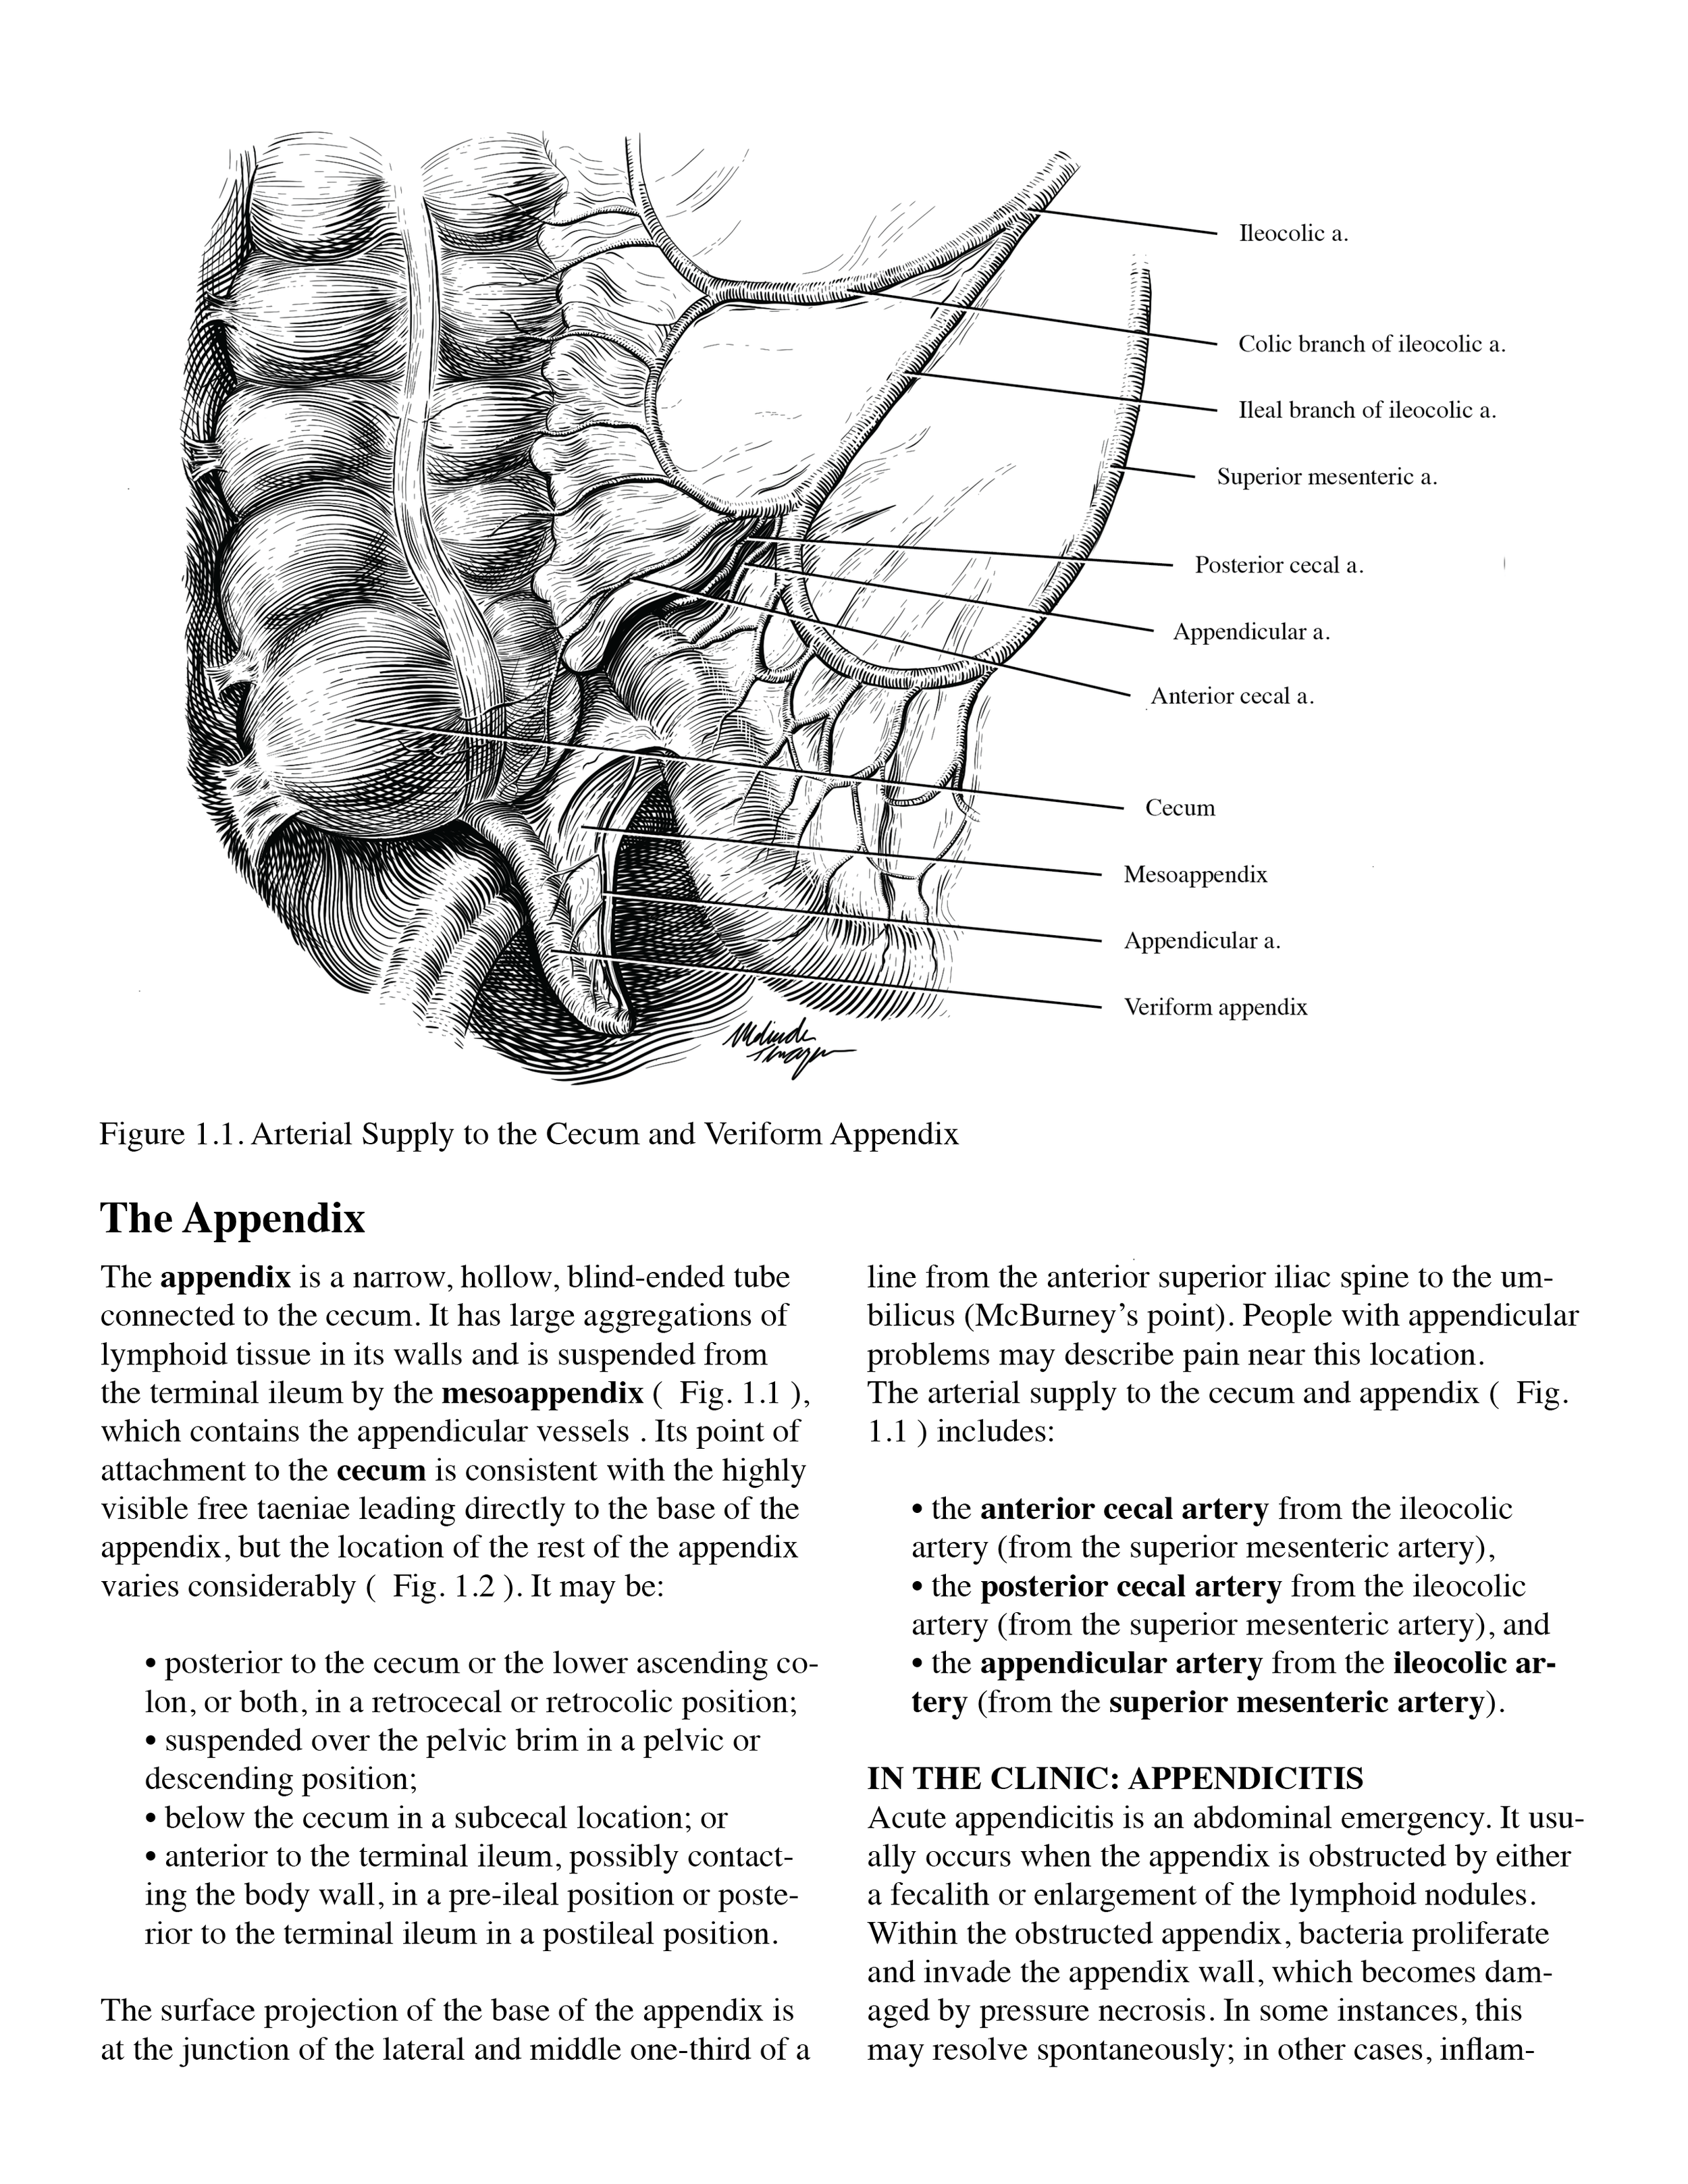

Textbook page: The Appendix